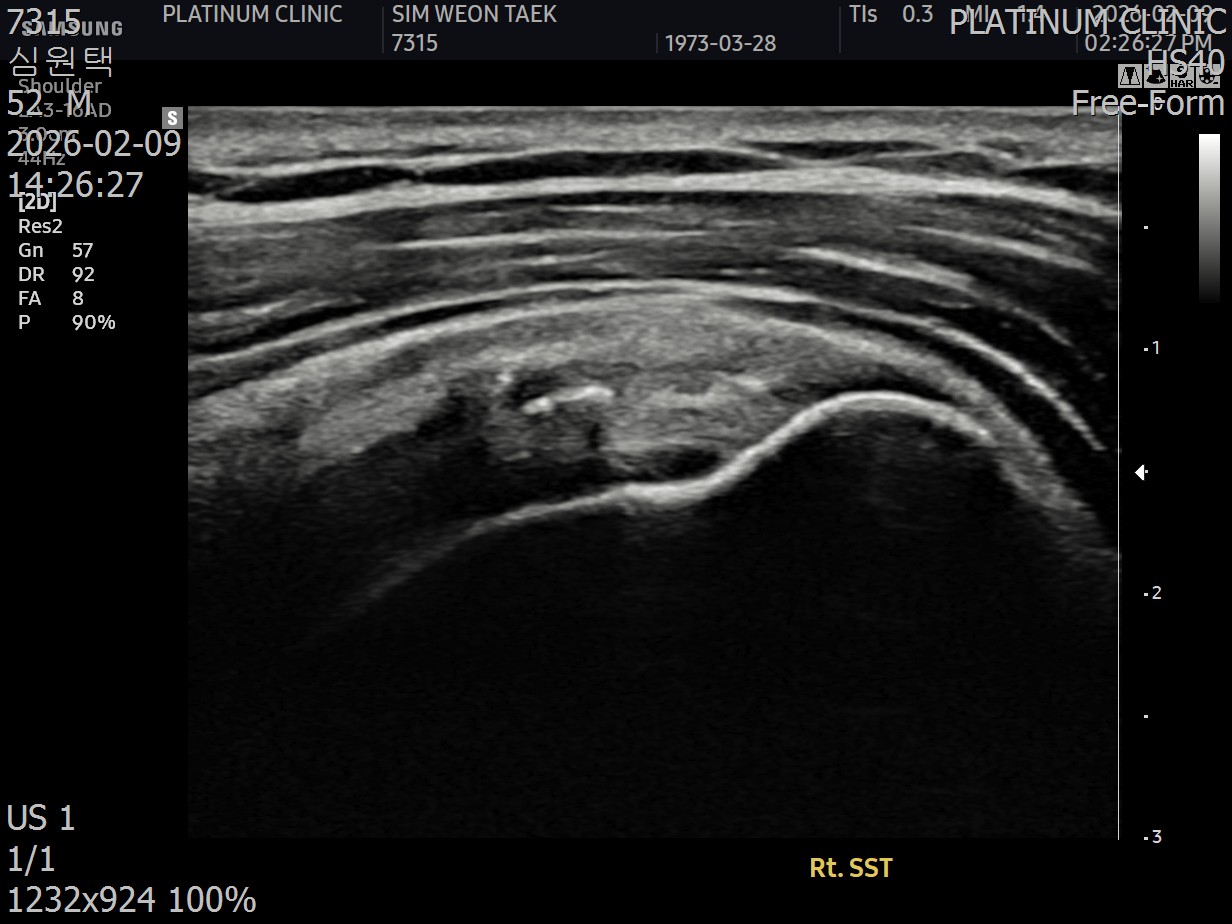

회전근개 힘줄 사이사이에 미세한 석회 침착이 여러 군데 흩어져 있었습니다. 크기가 매우 작아서 3mm 단위로 단면을 촬영하는 MRI에서는 보이지 않았지만, 초음파로는 선명하게 확인되었습니다.

근본 원인인 석회를 제거했습니다. 초음파로 확인된 미세석회들을, 석회분쇄흡입술을 통해 힘줄 사이사이에서 씻어내듯 제거했습니다.

초음파 검사에서도 석회는 깨끗이 사라졌고, 관절낭 유착도 재발하지 않았습니다.